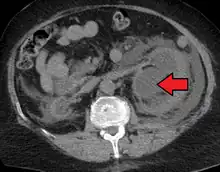

CT scan of bilateral hydronephrosis due to a bladder cancer

Massive hydronephrosis as marked by the arrow.- Renal ultrasonography of hydronephrosis[14]

- Stone causing hydronephrosis[14]

- Urine jets[14]